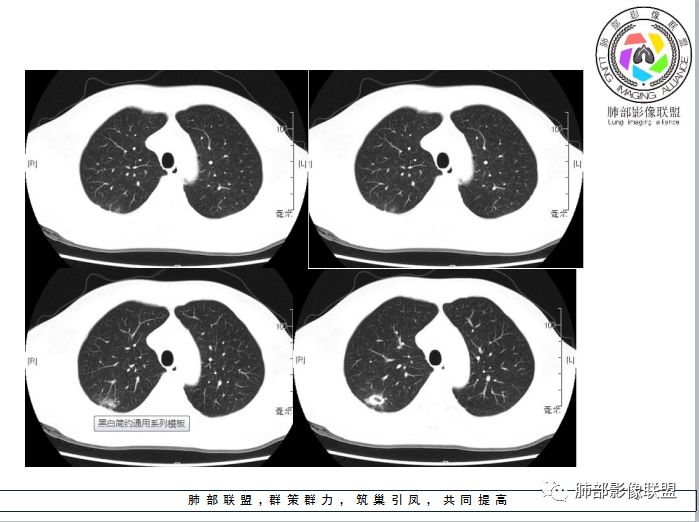

这个年龄无倾向性,啥都可以发生;有粉尘接触30年病史

背景似乎有些细小结节,又不是很明确

结合病史,尘肺有可能,把血管与这些结节样影鉴别开,我需要重建一下,

整体还规则,不能把长毛刺纳入进去,我们从周围朝内走吧

粗短毛刺价值就大,很犹豫,因为横断位看起来粗短,但是矢状位、冠状位似乎不是那么明显

哈哈,你看冠状位好像不明显,有没有可能假象啊,所以不踏实,我怕一个断面的假象,胸膜凹陷?这一条是可怕的

多发并行的线样胸膜牵拉是良性的特点。整体边缘有分叶吗?

近端支气管如何?进入结节内部支气管局部稍扩张

空洞吧,内壁光滑,偏肺门侧。这里我也不踏实,癌不能排除

再返回去看图,你会发现很多长条状的与胸膜相连的,我们叫胸膜牵拉征,连续的线状平行的是炎症的特点,这个结节是边缘光滑、类圆形的,长毛刺或条带状都是炎症的特点。

2、横断位你发现很多粗短毛刺:但是矢状位冠状位没发现了,是假的,所以我们要多方位、连续层面观察。3、支气管:进入病灶内的局部支气管扩张,符合炎症的。

4、边缘:病灶很多边缘平直、凹陷征,但是又感觉有些层面凹陷过深,炎症也可以,所以我们需要连续的图综合分析。

5、空洞:内壁光滑,近肺门侧空洞就是肺结核,肿瘤坏死是远端的,炎症都可以朝结核方面类似的;壁结节:如果层面稍微皱褶点,某些层面就成了壁结节。

划重点:多方位、连续层面去观察,空间思维去思考